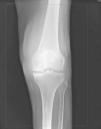

El motivo de escribir esta carta es describir el caso de una paciente con MM que desarrolló una artritis séptica de rodilla y una discitis lumbar tras una infección del tracto urinario. Se trata de una mujer de 81 años con antecedentes de uropatía obstructiva por nefrolitiasis que requirió ingreso en un hospital español y colocación de catéter pig-tail en agosto de 2008. Durante dicho ingreso presentó una bacteriuria asintomática tratada con cefixima oral. Un mes más tarde fue diagnosticada de MM de cadenas ligeras lambda estadio IIIB Durie-Salmon, Internacional Score System 3, y se inició tratamiento con pulsos de dexametasona mensuales y soporte eritropoyético semanal. En enero de 2009 acude a Urgencias de nuestro centro por dolor en la rodilla izquierda de 72 h de evolución sin traumatismo previo, fiebre ni otra clínica. En la exploración muestra signos de insuficiencia venosa crónica y gran aumento de volumen, signo de choque rotuliano, limitación articular y dolor a la movilización de la rodilla izquierda (fig. 1) con pulsos conservados. En la analítica: leucocitos 17,40×109/L (N 16.300; L 420); PCR 44,79 mg/L; dímero-D 3.179; IgG 593,00; IgA 45; IgM 20 mg/dL; ANA, ANCA y FR normales. VHB, VHC y VIH negativos. Se extrajeron hemocultivos. La radiografía de rodillas (fig. 2) descartó líneas de fractura e identificó un aumento inespecífico del realce perióstico en la meseta tibial medial izquierda, sin datos de esclerosis, e incremento de densidad de partes blandas periarticulares. La ecografía Doppler descartó trombosis venosa profunda. Realizamos una artrocentesis diagnóstico-terapéutica con colocación y mantenimiento de tubo de drenaje obteniéndose un líquido articular viscoso y turbio con aumento de leucocitos (95% polimorfonucleares), proteínas elevadas y glucosa disminuida. El Gram mostró bacilos Gram negativos, por lo que se instauró terapia empírica con ceftriaxona3 y se suspendieron los pulsos de dexametasona dada la presencia de infección documentada, con resolución sintomática, disminución del incremento de densidad radiológica periarticular y normalización de la PCR tras cuatro semanas de tratamiento. La caracterización final reveló que el microorganismo era E. coli. Una semana después reapareció el dolor y el aumento de volumen en la misma rodilla con nueva elevación de reactantes de fase aguda y nuevo aislamiento de E. coli en el líquido articular. Además, comenzó con febrícula, lumbalgia bilateral y espinopercusión positiva (L2-L3)4. La resonancia magnética de columna lumbar mostró discitis L3. Dado el empeoramiento clínico, se realizó artrotomía de rodilla con regular tolerancia, aunque con buena respuesta posterior. Tras valorar el riesgo/beneficio de un nuevo procedimiento invasivo y observar la excelente respuesta clínica y radiológica que experimentó tras reintroducir ceftriaxona5,6 –posteriormente el antibiograma confirmó sensibilidad a cefalosporinas de 3.a generación–, la lesión discal no fue biopsiada a pesar de ser conscientes de que hubiese sido lo más deseable para una correcta caracterización etiopatológica. No obstante, debido a la secuencia temporal, presumimos que el foco infeccioso inicial fue urinario y que una bacteriemia asintomática posterior facilitó la siembra de origen hematógeno en la rodilla y probablemente en el disco intervertebral, por lo que asumimos que la etiología fue la misma que ocasionó la monoartritis7.